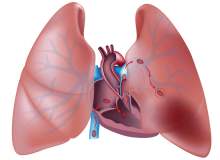

Akciğer Embolisi Teşhis Yöntemleri

Akciğer embolisinin teşhisi, özellikle arkasında kalp veya akciğerle ilgili bir rahatsızlık yatıyorsa zordur. Bu yüzden doktorunuz, belirtilerinizin nedenini bulmak için sizden bir dizi test yaptırmanızı isteyebilir.